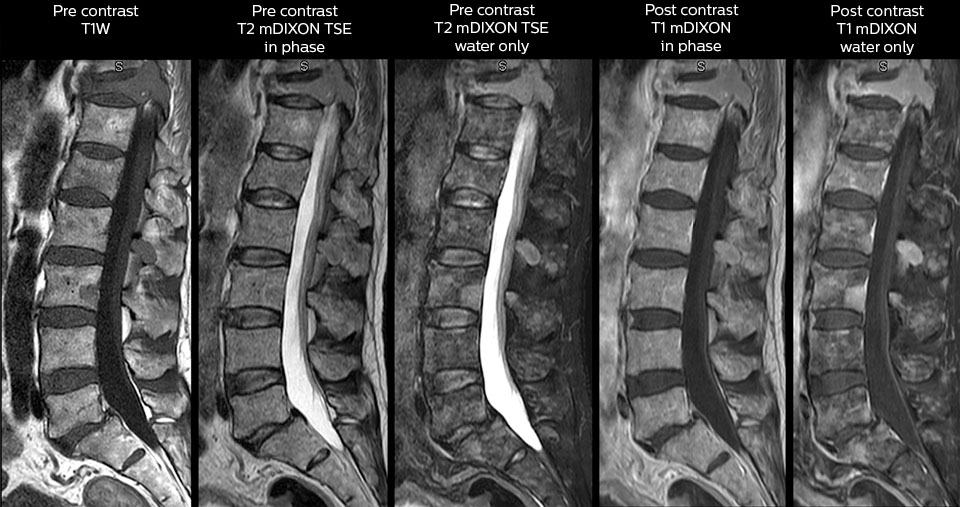

in image acquisition and postprocessing algorithms.”“mDIXON TSE sequences allow simultaneous characterization of morphological changes from the in-phase T2-weighted images and visualization of edematous changes, thanks to the water T2-weighted images from the same acquisition. Anatomical and morphological considerations could be a partial or complete ligament tear, a bony avulsion or hematoma.” “For soft tissue assessment mDIXON brings similar benefits. For example in one T2-weighted mDIXON TSE acquisition, having the multiple contrasts helps us assess abnormalities in peripheral nerves fascicles, which may be due to anatomical or inflammatory changes..” “In peripheral joints, we get good image quality in difficult areas with mDIXON TSE. Fat suppressed images appear homogeneous over the entire image, even with large coverage at 3.0T – for instance in scapular or hip girdles – or in the bearing areas or around metal prostheses*, where fat suppression is often deficient with STIR or spectral fat suppression, causing diagnostic difficulties. If a diagnostic image is right the first time, we don’t need to repeat or add a sequence.” “mDIXON TSE sequences allow simultaneous characterization of morphological changes from the in-phase T2-weighted images and visualization of edematous changes, thanks to the water T2-weighted images from the same acquisition. Anatomical and morphological considerations could be a partial or complete ligament tear, a bony avulsion or hematoma.” “For soft tissue assessment mDIXON brings similar benefits. For example in one T2-weighted mDIXON TSE acquisition, having the multiple contrasts helps us assess abnormalities in peripheral nerves fascicles, which may be due to anatomical or inflammatory changes..”

“We use mDIXON TSE extensively in our spine imaging in the emergency room,” says Dr. Karis. “It’s particularly nice in that it is very robust with regard to susceptibility type of problems that would come up with traditional spectral fat-saturated images; these problems are essentially eliminated with the mDIXON technique. In our ED environment it’s really nice to have the fat-free imaging that goes along with the mDIXON technique.

“For the thoracic and cervical spine routine non-contrast exam, for example, we perform one mDIXON T2 TSE sequence, which provides us with two outputs: the fat-and-water-together T2-weighted images, as well as the water-only sagittal T2-weighted images. And then we also perform an axial gradient echo exam.”